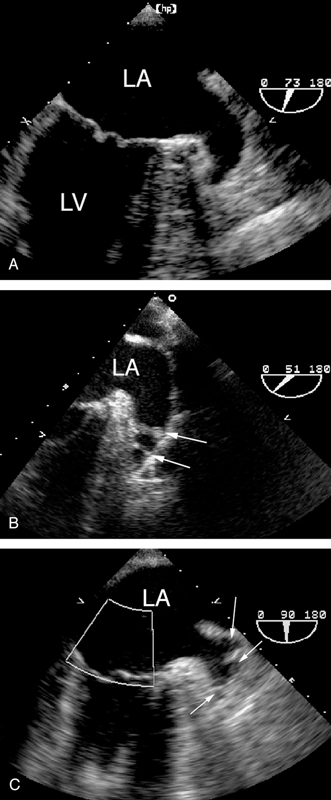

فحوصات تشخيصية لبعض امراض القلب والشرايين التاجية